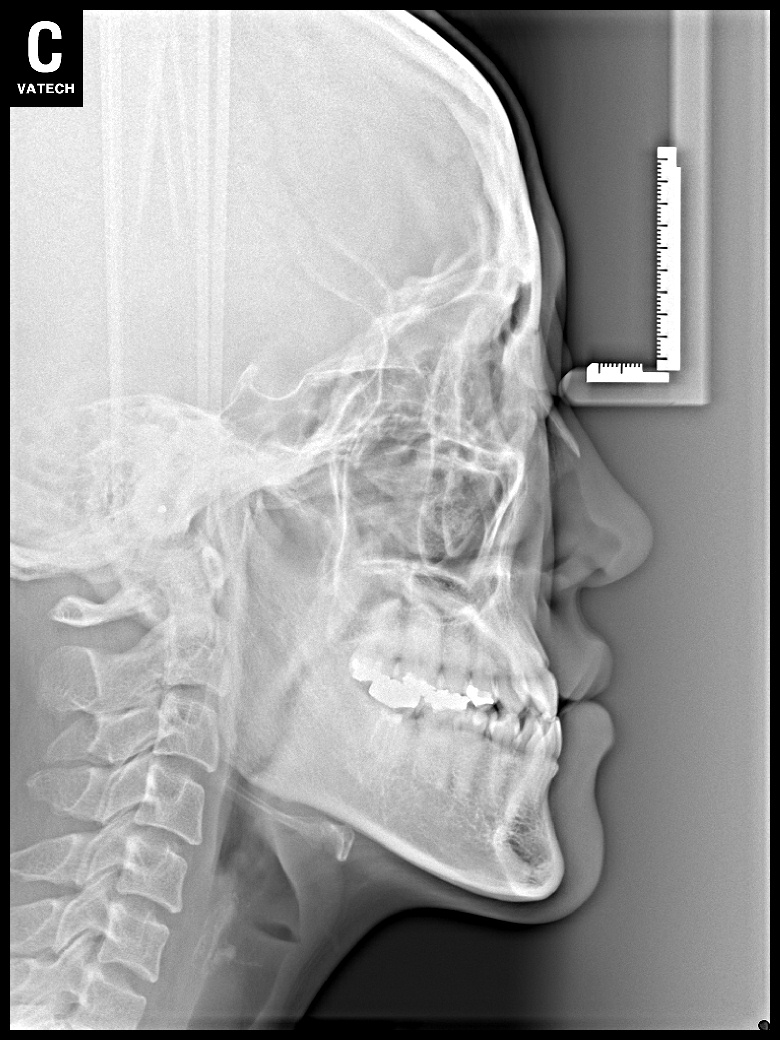

치료 전 사진입니다.